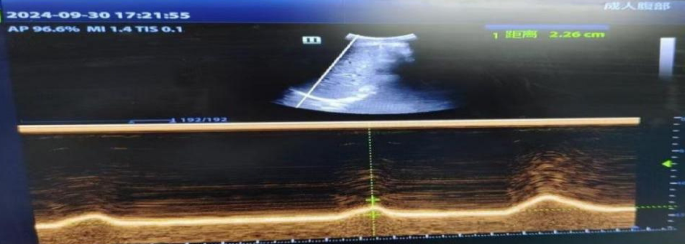

① Diaphragmatic mobility

Refers to the difference in displacement distance of the diaphragm at the end of exhalation and inhalation. The patient is in a supine position, with the convex array probe placed at the junction of the midline of the clavicle and the lower edge of the rib arch. The liver is used as the sound window, and the probe is perpendicular to the diaphragm dome. The ultrasound beam is directed toward the head and left and right scans are performed to locate the position of the diaphragm. On the B-mode ultrasound image, select the location with the highest motion amplitude, make the sampling line perpendicular to the diaphragm, convert it to M-ultrasound, and display the trajectory of the diaphragm along the sampling line with respiratory movement. Adjust the scanning speed according to the subject’s respiratory rate, record the difference in distance between the end-expiratory and end-inspiratory phases and the sampling line, measure three times, and take the average. See Fig. 3.

Schematic diagram of diaphragm movement measurement (right side).